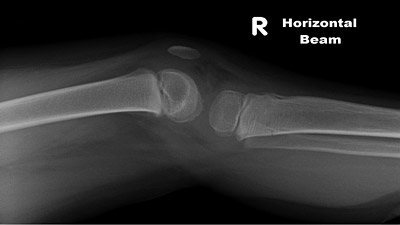

Patient is a 5-year-old with a transverse fracture of the proximal tibial metaphysis ("trampoline fracture"). The injury occurred while jumping on a trampoline with his father.